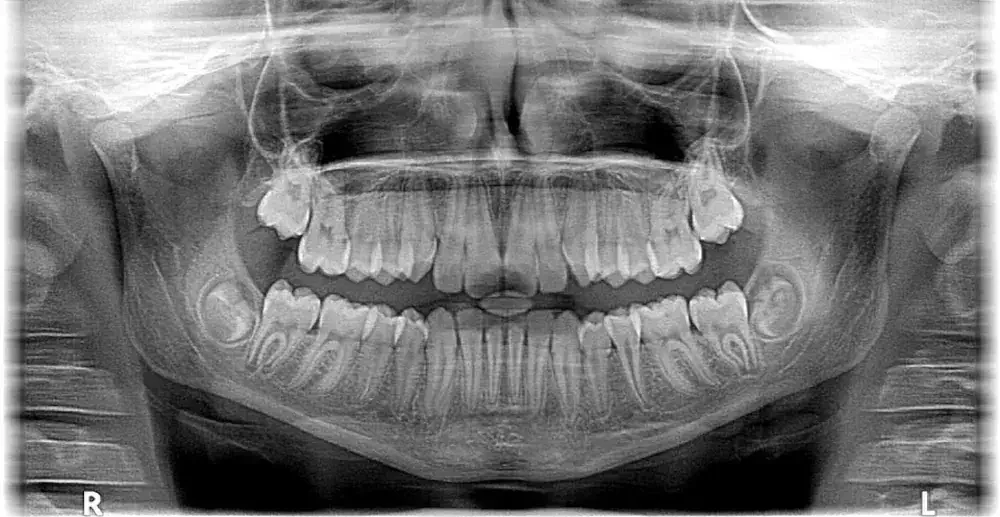

X-ray gigi atau rontgen gigi membantu dokter gigi melihat kondisi gigi dan jaringan di bawahnya yang tidak dapat terlihat dengan mata. Misalnya akar gigi, tulang rahang, gigi berlubang yang tersembunyi, hingga tanda infeksi atau peradangan.

Dalam praktiknya, pemeriksaan X-ray gigi terdiri dari beberapa jenis, seperti digital X-ray (periapical) yang digunakan untuk melihat detail satu atau dua gigi secara spesifik, panoramic X-ray untuk gambaran seluruh gigi dan rahang, serta CBCT yang memberikan visualisasi tiga dimensi untuk kebutuhan perawatan tertentu. Jenis pemeriksaan yang digunakan akan disesuaikan dengan kondisi dan kebutuhan pasien

Teknologi X-ray gigi yang modern mampu menghasilkan gambar yang lebih jelas dengan paparan radiasi minim. Hasil rontgen yang tajam akan sangat membantu dokter gigi dalam melihat kondisi akar gigi, tulang rahang, hingga infeksi yang tidak tampak dari pemeriksaan biasa.

Pemeriksaan ini memungkinkan dokter gigi melihat kondisi gigi, akar, dan struktur tulang rahang secara lebih detail sebelum menentukan rencana perawatan.

Melalui teknologi Digital X-Ray dan CBCT, dokter gigi dapat memperoleh visualisasi yang lebih jelas, termasuk gambaran tiga dimensi, dengan paparan radiasi yang lebih minimal.